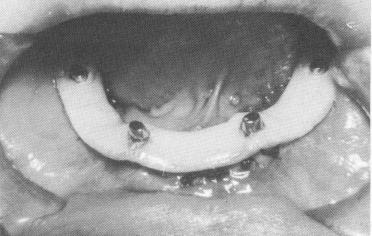

Fig. 12-25. Sometimes one to three small set screws are used to stabilize the implant to the bone.

The holes for the screws are located in the parts of the implant that will cover the densest bone: both external oblique ridges posteriorly and the symphysis anteriorly (Fig. 12-25). Before each screw is set, a small hole is made with a No. 556 fissure bur at right angles to the surface of the bone. While inserting the screws the operator must make sure that they are going in exactly the same direction as the walls surrounding them. Otherwise the screws can create a degree of torque that will either distort the implant itself or interfere with its accurate fit and cause rapid bone resorption. Once the tissues over-lying the implant have healed, the screws can be re-moved, if desired, but this is not necessary. A special Vitallium screwdriver is sometimes used for this procedure.